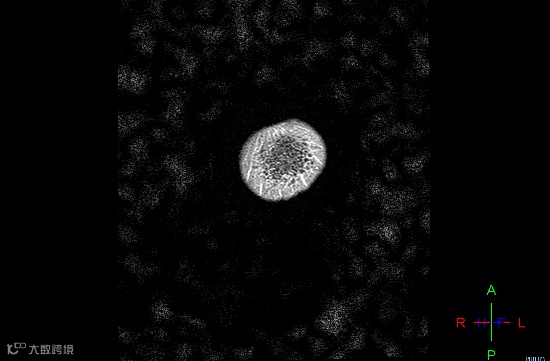

左:头部失状扫描图;右:假牙干扰后的伪影

③ 在进行盆腔检查中,金属节育器可能会引起图像失真。